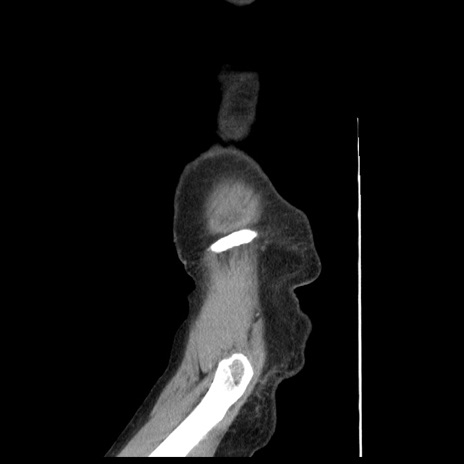

冠状断像

【症例】80歳代女性

【主訴】腹痛

【現病歴】8時間前から腹痛あり来院。

【既往歴】糖尿病、脂質異常症、子宮体癌にて子宮全摘術

【身体所見】意識清明・会話良好だが腹痛で苦悶様、全腹部にわたって反跳痛と圧痛あり

【データ】WBC 13600、CRP 0.14、LDH 224、CK 90